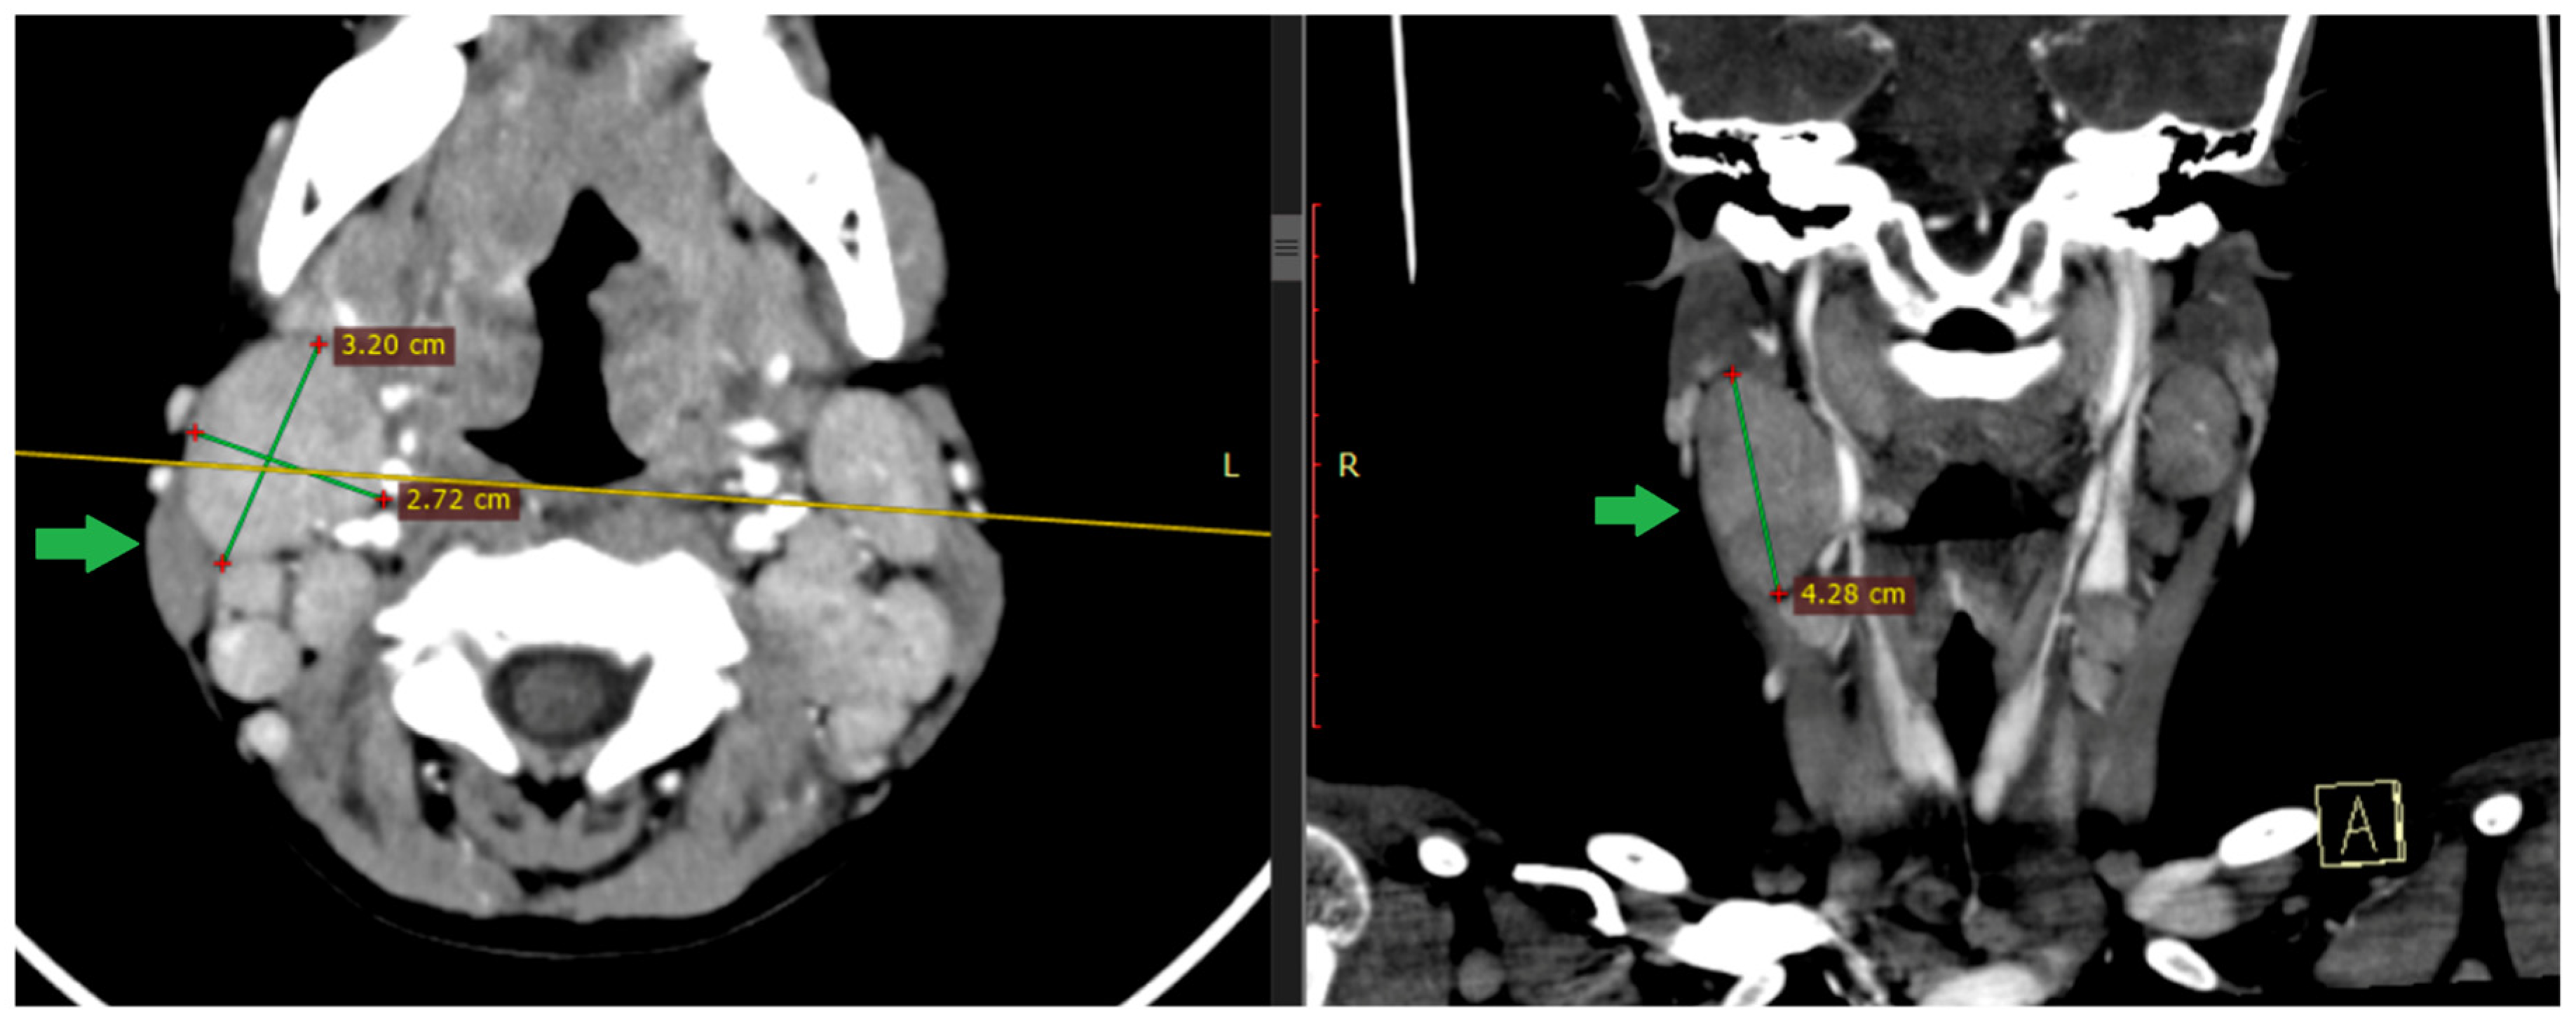

2.1. Case 1